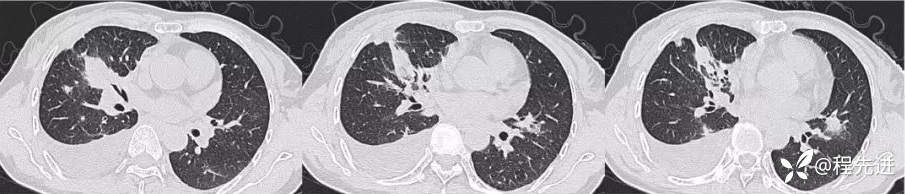

CT平扫:

肺窗